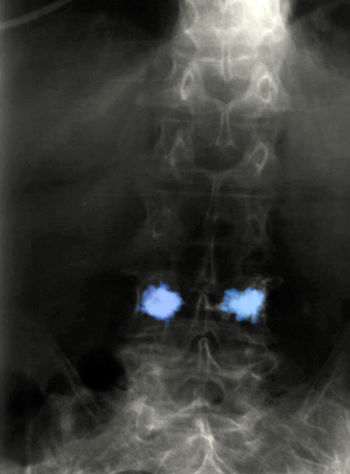

Spondyloplasty1

Σπονδυλοπλαστική οσφυϊκού σπονδύλου.